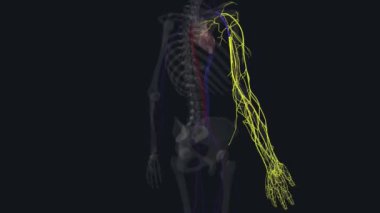

SağlıkkanİlaçkalpStetoskopTedaviHastalıkbiyolojiGöğüsorgİyileştiriyorvenanatomibelirtileriobstrüksiyonarterkapillerkasılmaAtriumGöğüs kemiğiaortKalp kriziKalp kasıGöğüs Ağrısıkalp zarınıKan damarıStentkan akımıacil tedaviKoroner artersol ventrikülSağ ventrikülkalp ilacıdiyaframdanKalp kapakçığıkardiyovasküler sistemSol atriyumPulmoner dolaşımSistemik dolaşımPulmoner arterSağ atriumsemilunar valvepulmoner venbicuspid valvepapillary musclecardiac septumcardiac wallheart catheterisationBenzer İçerikler